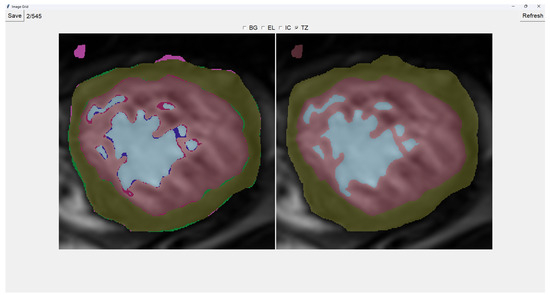

This program presents two images as shown in Figure 3. The image on the left is obtained from our previous method (QLVTHC), while the one on the right is obtained from our neural networks (Section 2.1). The final output of our program is the segmentation on the right.

We use a muted color scheme to make the colors distinguishable for colorblind people. In the image on the right, the External Layer is olive green, the Internal Cavity is cyan, and the Trabecular Zone is rose.

On the figure on the left, we mark the differences between both segmentations. This way, where there is an External Layer on the left and something else on the right, we mark it with green. For additional Internal Cavity, we mark it with blue; for Trabeculae, we mark it with wine red; for Background, we mark it with purple.

The differences between both images can be leveraged for easy transformations of the output image. The transformation is applied to the image on the right by simply clicking one of the differences. For example, if we click a blob that is colored green on the left (meaning an additional External Layer), an External Layer will appear in that zone of the image on the right. Some of these blobs are very small, so you can select them by right-clicking and dragging over them for ease of use.

Painting directly on the output image (the image on the right) is also possible. For this, we select either BG (Background), EL (External Layer), IC (Internal Cavity), or TZ (Trabecular Zone). Then, we simply left-click where we want to paint (as shown in Figure 4).

Finally, we can also toggle the segmentation which helps us view the borders’ coloring. It is important to note that you can still paint when the image is toggled to the raw image.